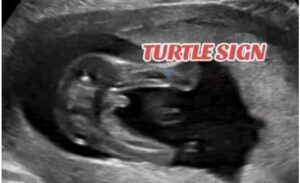

يستطيع الطبيب المساعدة على تحديد نوع الجنين بالبحث عن شكل اعضاء الجنين الذكر والتي تظهر في تصوير السونار بشكل غطاء السلحفاة وتسمى علامة السلحفاة turtle sign كما يتضح في الصورة التالية.